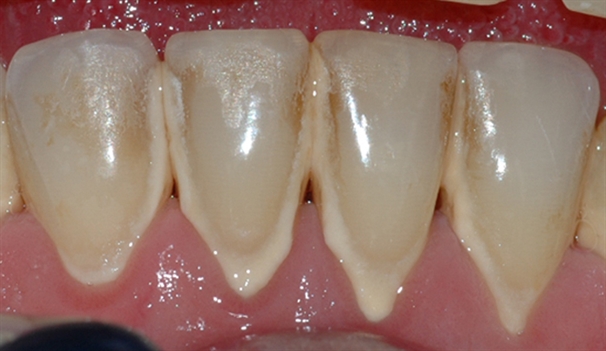

Bildet viser et tannsett med synlig tannsten og misfarging.

Bildet viser et nærbilde av tennene i underkjeven med tannsten og misfarging.